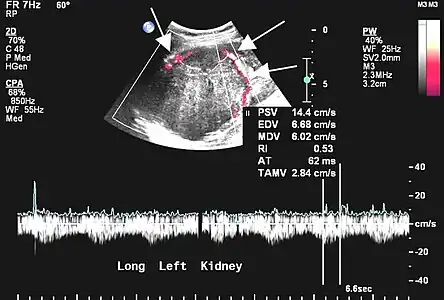

L'échographie est rarement réalisée pour les localisations pleurales, mais peut être utile dans les autres localisations[45]. Les tumeurs fibreuses solitaires se présentent comme des masses homogènes, hypoéchogènes et bien délimitées ; le doppler permet de visualiser la vascularisation. Les tumeurs pleurales se mobilisent avec les mouvements ventilatoires[45].

Aspect échographique. La vascularisation est visible en rouge, repérée par les flèches[46].